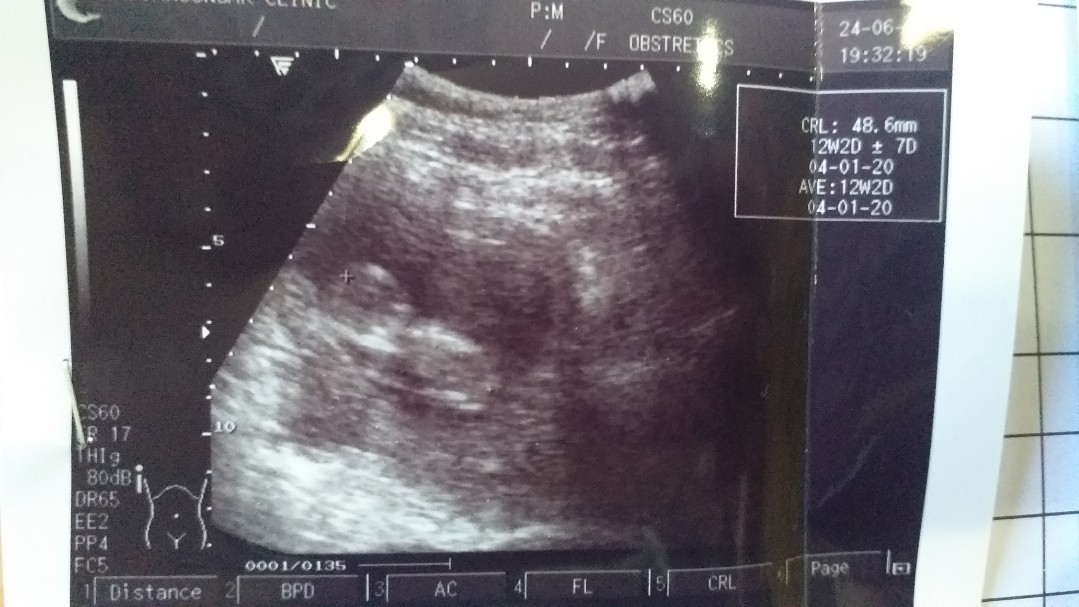

12w2dค่ะ

VIP Member